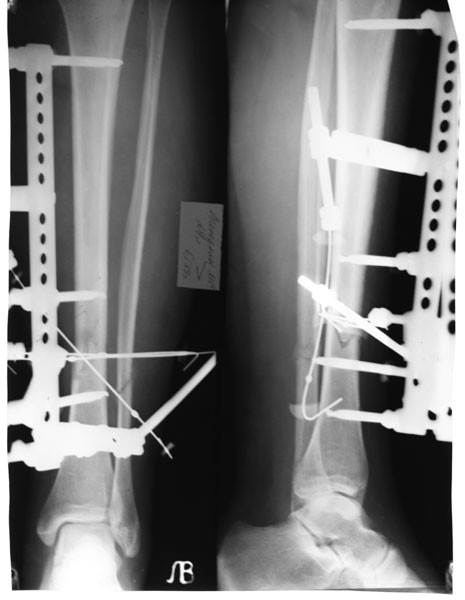

Аппараты внешней фиксации (чрескожная методика)

Методика позволяет репозиционировать и тщательно зафиксировать отломки, не обнажая область перелома.

Ее суть – проведение через костную ткань стержней или спиц, фиксирующихся снаружи в специальном аппарате. Сейчас есть монолатеральные, циркулярные, секторные, полуциркулярные, билатеральные и комбинированные аппараты. Предпочтение чаще отдается стержневым моделям. Использование внешних фиксаторов – незаменимый способ лечения высокоэргичных травм, например минно-взрывных, огнестрельных, которые сопровождаются значительными повреждениями как костей, так и мягких тканей. Периферическое кровоснабжение конечности должно быть сохранено.